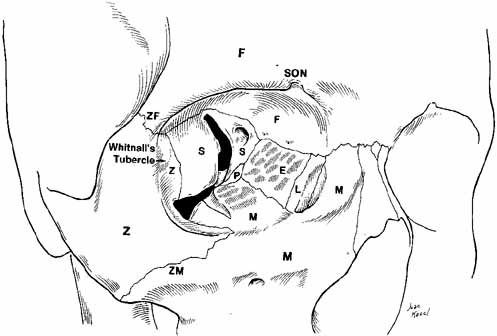

Fig. 11 Superior view of the orbit. Whitnall's ligament fuses medially with

the trochlea of the superior oblique muscle and fuses laterally with

the lacrimal gland. The medial horn of the levator aponeurosis lies directly

on top of the superior oblique reflected tendon. The lateral horn

of the levator aponeurosis splits the palpebral and orbital lobe of

the lacrimal gland. The lateral rectus check ligament attaches to Whitnall's

tubercle and is slightly denser than the medial rectus ligament. (WL, Whitnall's ligament; OLG, orbital lobe of lacrimal gland; SOT, superior oblique tendon; PAFP, preaponeurotic fat-pad; LM, levator palpebrae superioris muscle; WT, Whitnall's tubercle; MRM, medial rectus muscle; LRM, lateral rectus muscle; SRM, superior rectus muscle) Fig. 11 Superior view of the orbit. Whitnall's ligament fuses medially with

the trochlea of the superior oblique muscle and fuses laterally with

the lacrimal gland. The medial horn of the levator aponeurosis lies directly

on top of the superior oblique reflected tendon. The lateral horn

of the levator aponeurosis splits the palpebral and orbital lobe of

the lacrimal gland. The lateral rectus check ligament attaches to Whitnall's

tubercle and is slightly denser than the medial rectus ligament. (WL, Whitnall's ligament; OLG, orbital lobe of lacrimal gland; SOT, superior oblique tendon; PAFP, preaponeurotic fat-pad; LM, levator palpebrae superioris muscle; WT, Whitnall's tubercle; MRM, medial rectus muscle; LRM, lateral rectus muscle; SRM, superior rectus muscle)